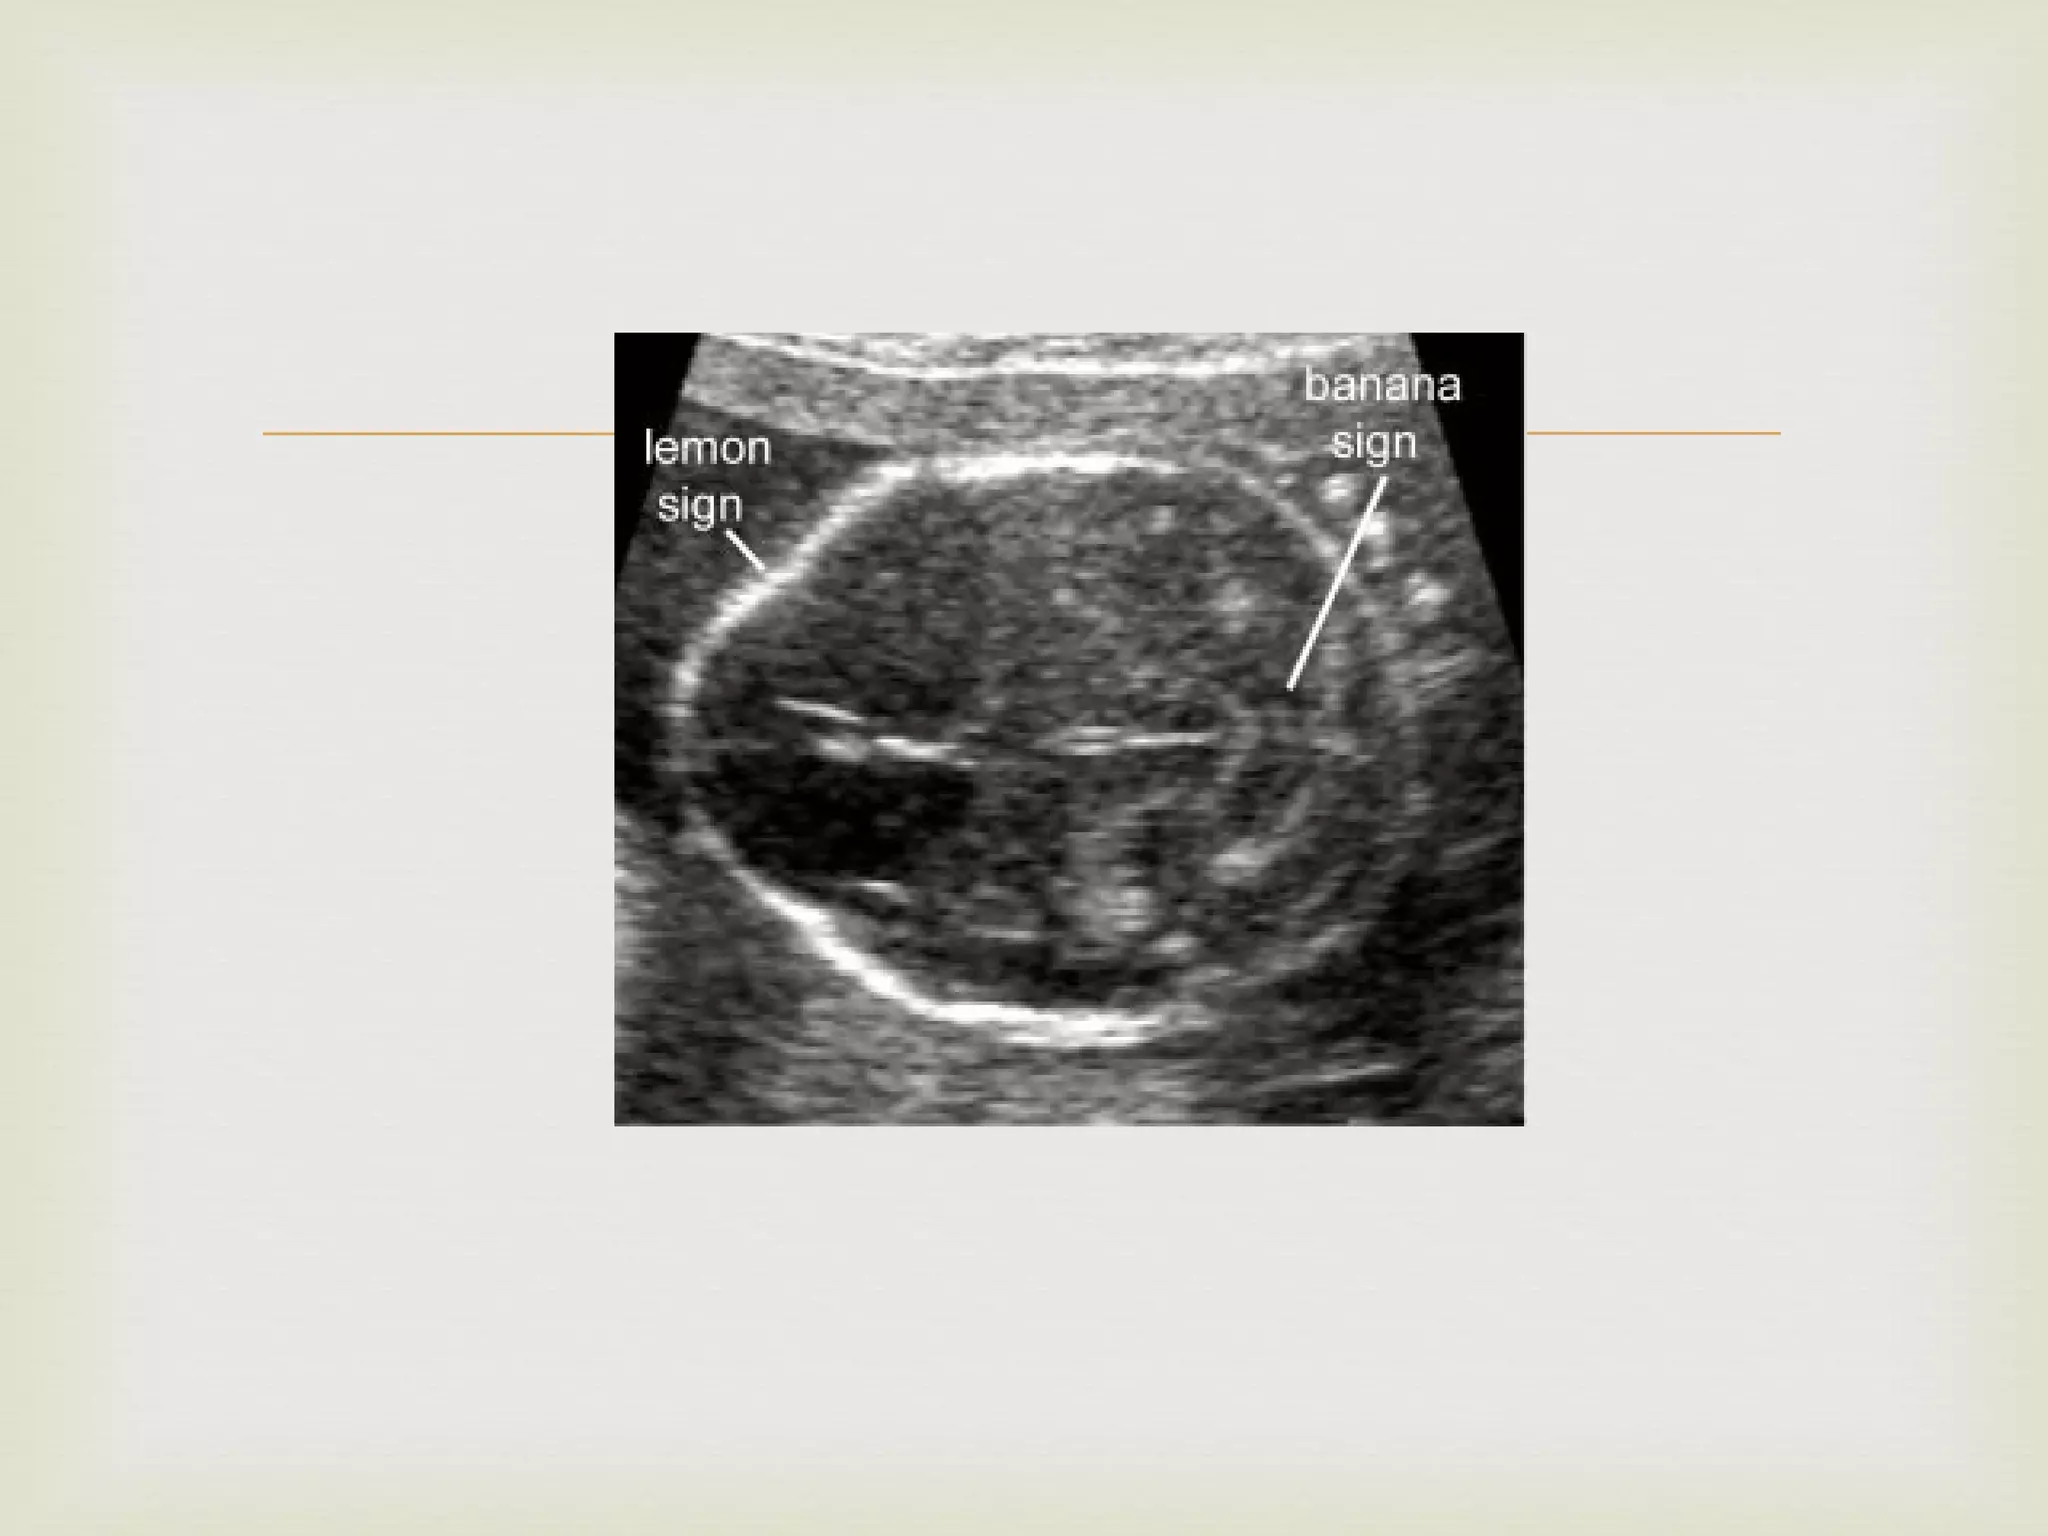

In 54 fetuses who had pictures taken at BPD plane showed scalloping of the frontal bones ( Lemon Sign )

In 12 of the 21 fetuses for which sub occipito bregnatic plane was taken, showed cerebellar hemispheres curved anteriorly with simultaneous obliteration of Cisterna Magna ( Banana Sign )

None of these changes were present in 100 normal  fetuses

Lemon sign & Banana sign present in 100% of cases diagnosed as open neural tube defect between 16-24 weeks Detected 1-2 weeks before noticing spinal defect Microcephaly in 69%

After 24 weeks, Lemon sign noted only in 25% Microcephaly and Banana sign noted in 100%